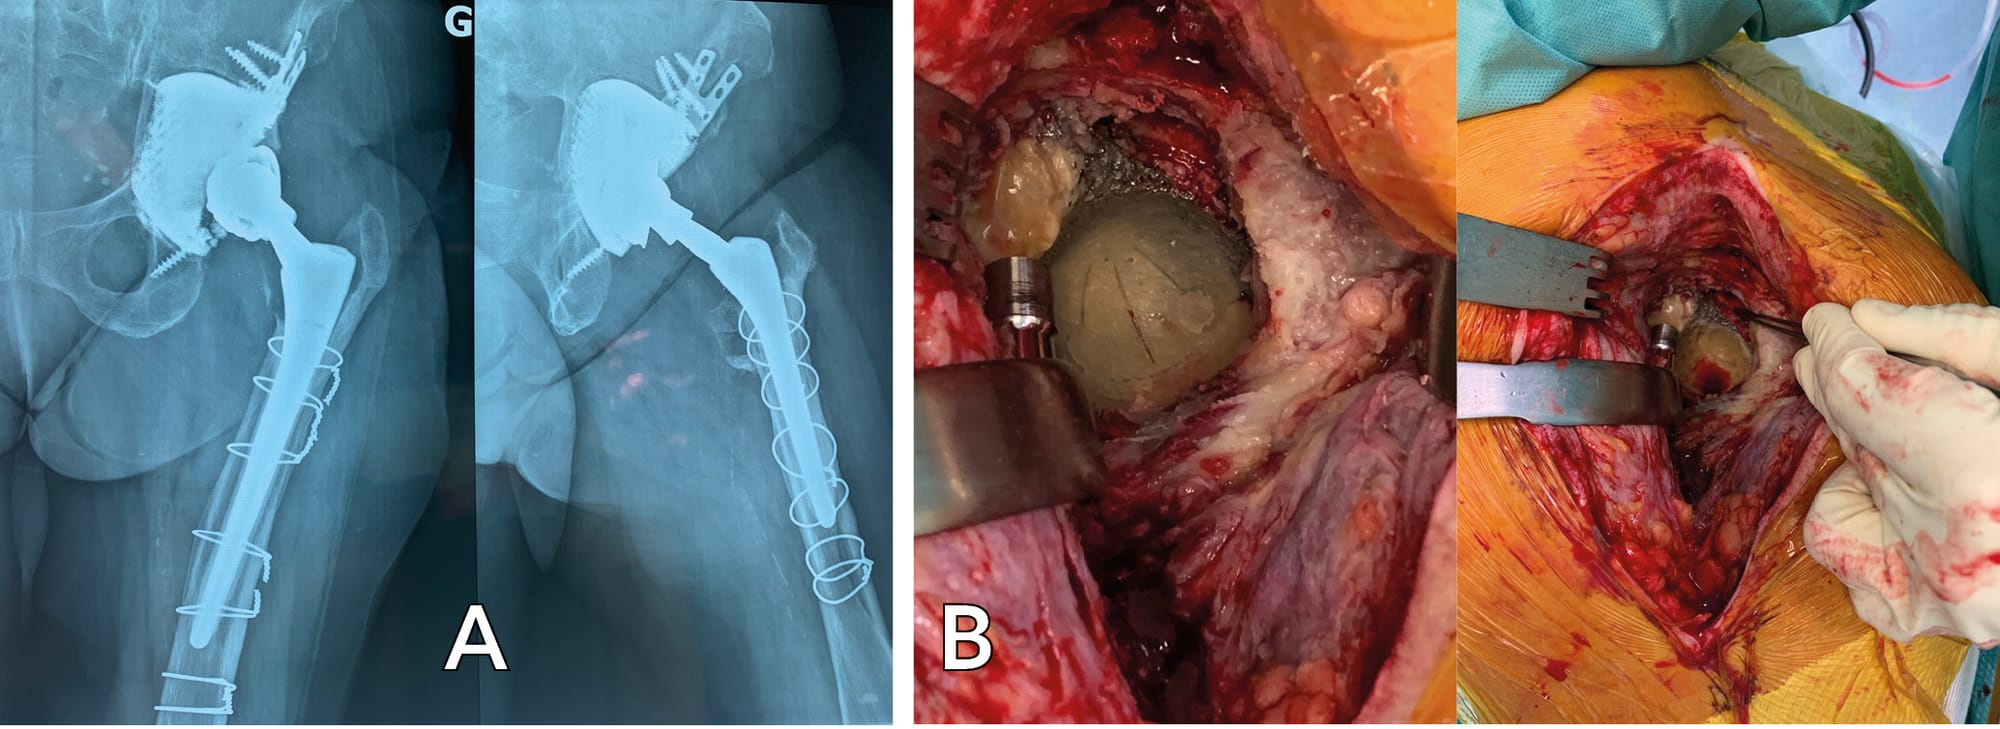

Two patients underwent partial revision: the DM component and two mobile parts were changed without revising the custom-made implant. During this process, we noted that these uncemented implants were perfectly intact and stable two months after they were fitted.

Loosening of a cemented DM component after a fall with 3D-printed implant remaining in place

Eight years after acetabular revision, a fall led to loosening of a dual mobility implant without compromising fixation of a 3D-printed implant.

In this unusual situation, the 3D-printed implant remained in place and the remnants of DM cement were removed manually and by additional reaming. The hemispherical interface was drilled to make perforations and a further cemented dual mobility component was fitted (Figure 16).

There was excellent immediate recovery in this case and the functional outcome remained highly satisfactory after 3 years.

We performed two explantations due to failed treatment of an infection and a new infection. Both of these implants had complex, non-hemispherical geometry. These extractions were performed using a Cauchoix osteotome with no significant bone loss. The anchoring was very good. A histopathological analysis was performed which found mainly fibrous tissue at the contact interface with the removed implant. (Figure 17)